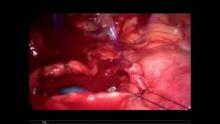

The authors present a case of uniportal VATS for repair of an iatrogenic tracheal injury. The patient was a 90-year-old woman who developed progressive subcutaneous emphysema after laparoscopic cholecystectomy. A double-lumen tube was immediately inserted to control subcutaneous emphysema. Then she was transferred to the authors’ unit for further evaluation and treatment. A bronchoscopy was performed under general anesthesia and a tracheal injury was detected in the distal part of the trachea extending to the right main bronchus. A decision was made to perform a surgical repair, and she was re-intubated with a left double lumen tube and taken to the operation room. Uniportal VATS was performed through a 4 cm incision in the 5th intercostal space in the mid-axillary line. The azygos vein was divided using an endo-stapler to reveal the tracheobronchial angle. A tracheal injury 5 cm long was identified on the right side of the distal trachea extending to the right main bronchus. Stay sutures were placed on both edges to expose meticulously the proximal and distal end of the injury. The tracheal injury was repaired with 4-0 polypropylene suture using a continuous suture technique. The suture line was covered with paratracheal fatty tissue and the operation was completed after inserting a chest tube.

On the postoperative bronchoscopy, the trachea with visible suture lines was intact and healthy. She was extubated immediately after surgery and discharged home on the fourth postoperative day. After that, on routine follow-up, the patient was examined periodically. She did not have any complaints in this period and no evidence for stricture was observed. Three months after the surgery, the trachea was considered intact and healthy again, indicating that no complications have occurred.